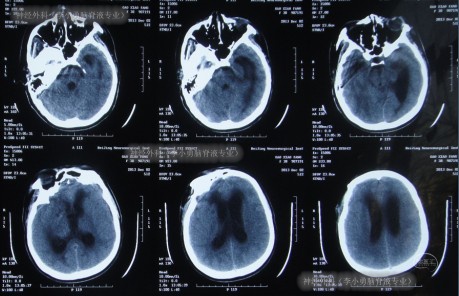

患者于2013年11月4日,突发剧烈头痛,难以忍受,前往北京某三甲医院进行头颅CT示蛛网膜下腔出血(图-1),随即进行头颅CTA检查确诊为右前交通动脉瘤(图-2)。

图-1:2013年11月4日

术后第4天即腰大池引流4天后复查头颅CT示右侧基底节区斑片状低密度影,和因腰大池引流脑室较前变小(图-3)。

图-3:术后4天头颅CT

2013年11月11日即术后7天时,患者中度昏迷,伴有呼吸困难,立即进行头颅CT检查发现了脑严重肿胀的表现(图-4)。

图-4:术后7天头颅CT